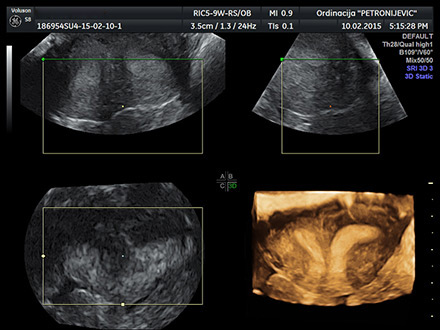

Ekspertski ultrazvuk

4D ultrazvuk

Ordinacija raspolaže 4D ultrazvučnim aparatom poslednje generacije, videokolposkopom, histeroskopom, kardiotokografom, a oprema se stalno obnavlja.